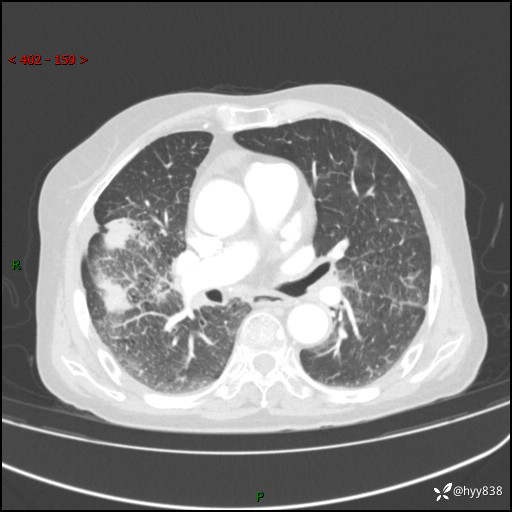

胸部CT增强(外院平扫)